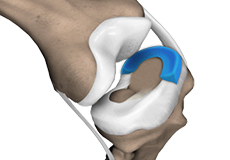

Traditionally, arthritis in only one compartment of the knee is treated by partial knee replacement surgery. Patellofemoral knee replacement is a minimally invasive surgical option performed in the patellofemoral compartment only, preserving the knee parts not damaged by arthritis as well as the stabilizing anterior and posterior cruciate ligaments (ACL and PCL).

Meniscal Surgery

Meniscal surgery is a surgical procedure employed for the treatment of torn or damaged meniscal tissues in the knee. It is mostly performed as a minimally invasive keyhole procedure.

Partial Arthroscopic Meniscectomy

Partial arthroscopic meniscectomy is a procedure to remove the damaged part of a meniscus in the knee joint with the help an arthroscope. The meniscus is a C-shaped disc of cartilage between your thighbone and shinbone.

Partial Meniscectomy

Partial meniscectomy is a surgical procedure to remove the torn portion of the meniscus from the knee joint. Meniscal tears can occur at any age, but are more common in athletes playing contact sports. These tears are usually caused by twisting motion or over-flexing of the knee joint.